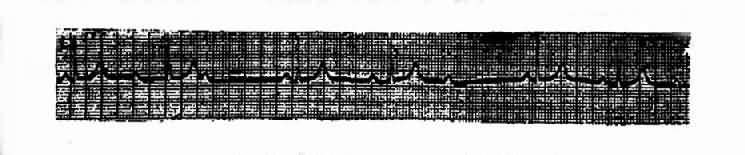

(二)第二度Ⅱ型房室传导阻滞莫氏Ⅱ型①P-R间期固定,可正常或延长。②QRS波群有间期性脱漏,阻滞程度可经常变化,可为1:1;2:1;3:1;3:2;4:3等。下传的QRS波群多呈束支传导阻滞图型。(图3-3-21)

图3-3-21 Ⅱ度Ⅱ型房室传导阻滞(莫氏Ⅱ型)

第一度和第二度Ⅰ型房室传导阻滞,阻滞部位多在房室结,其QRS波群不增宽;第二度Ⅱ型房室传导阻滞,其阻滞部位多在希氏束以下,此时QRS波群常增宽。